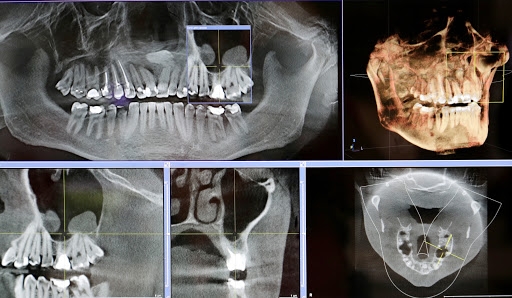

Lo Studio è dotato di un moderno sistema di radiologia digitale NewTom 3D TC di ultima generazione Cone Beam che in soli 15/20 minuti esegue un completo esame tridimensionale. Progettato dai pionieri del CBCT 3D in ambito dento-maxillofacciale, NewTom offre le migliori performance e la straordinaria qualità dell’imaging 3D. Direttamente nel vostro studio di fiducia, è possibile eseguire esami radiografici completi del complesso maxillofacciale con tecnologia UHD digital di ultima generazione a ridotta emissione di radiazioni per esposizione.

Sezioni Tomografiche (TC/Tac) e Ricostruzioni 3D dei mascellari Ortopantomografia delle arcate dentarie a bassa emissione di radiazioni X Ortopantomografia delle arcate specifica per uso pediatrico Rx Stratigrafia dei condili mandibolari compresa ATM Emimandibola dx/sx Adatta per adulti e bambini, veloce e indolore, consente di ottenere in tempo reale i referti necessari per le diagnosi e la pianificazione delle cure. Lo specialista garantisce le stesse tariffe applicate presso le strutture sanitarie specializzate esterne pur offrendo un prodotto avanzato, confortevole e sicuro.